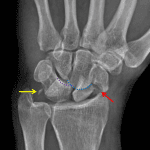

- Acute scaphoid waist fracture with 5 mm radial displacement of the distal fracture fragment

- Osseous fragments along the dorsal margin of the distal radius

- Rounded metallic foreign body in the soft tissues along the volar aspect of the third metacarpal

Osseous fragments along the dorsal margin of the distal radius may represent shear fractures from Lister’s tubercle or from the dorsal lunate.

Rounded metallic foreign body in the soft tissues along the volar aspect of the third metacarpal.